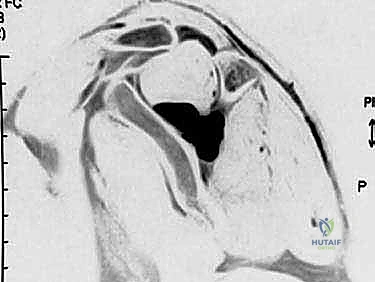

3. التصوير بالرنين المغناطيسي (MRI)

* الكشف عن الآفات الشاغلة للحيز مثل الكيسات العقدية (Ganglion cysts) بدقة متناهية.

* تقييم حالة العضلات (هل هناك تغيرات دهنية أو ضمور لا رجعة فيه؟).

* تقييم حالة أوتار الكفة المدورة والشفا الغضروفي (لتحديد سبب تكون الكيسة إن وجدت).

- انضغاط الشق فوق الكتفي (العلوي): يؤدي إلى ألم شديد، مع ضعف وضمور في كلتيهما (العضلة فوق الشوكة والعضلة تحت الشوكة).

- انضغاط الشق الشوكي الحقاني (السفلي): يؤدي غالبًا إلى ضعف وضمور في العضلة تحت الشوكة فقط، مع ألم أقل أو معدوم.